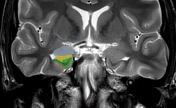

Amygdalotomy

Specialized surgery targeting amygdala for PTSD relief.